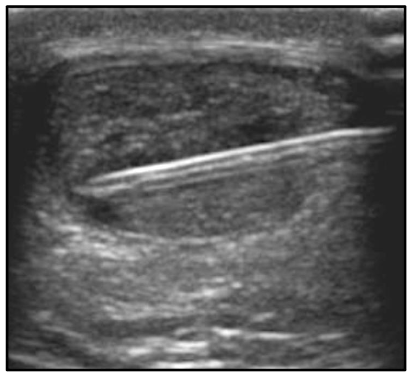

Magnetic resonance imaging (MRI) confirmed the US findings, with midportion Achilles tendinosis and a large partial-thickness interstitial tear (18 x 4 x 3mm). Pathology and treatment options were discussed, and he decided on a sequential, staged treatment approach that included percutaneous ultrasonic tenotomy, connective tissue matrix injection, and a bone marrow concentrate procedure.

Figure 1: Fat suppressed T2-weighted magnetic resonance image of the distal leg with an arrow showing an 18 x 4 x 3 mm hyperintense lesion in the midportion Achilles tendon, consistent with an interstitial partial tear. (A) is the axial view and (B) is the sagittal view.